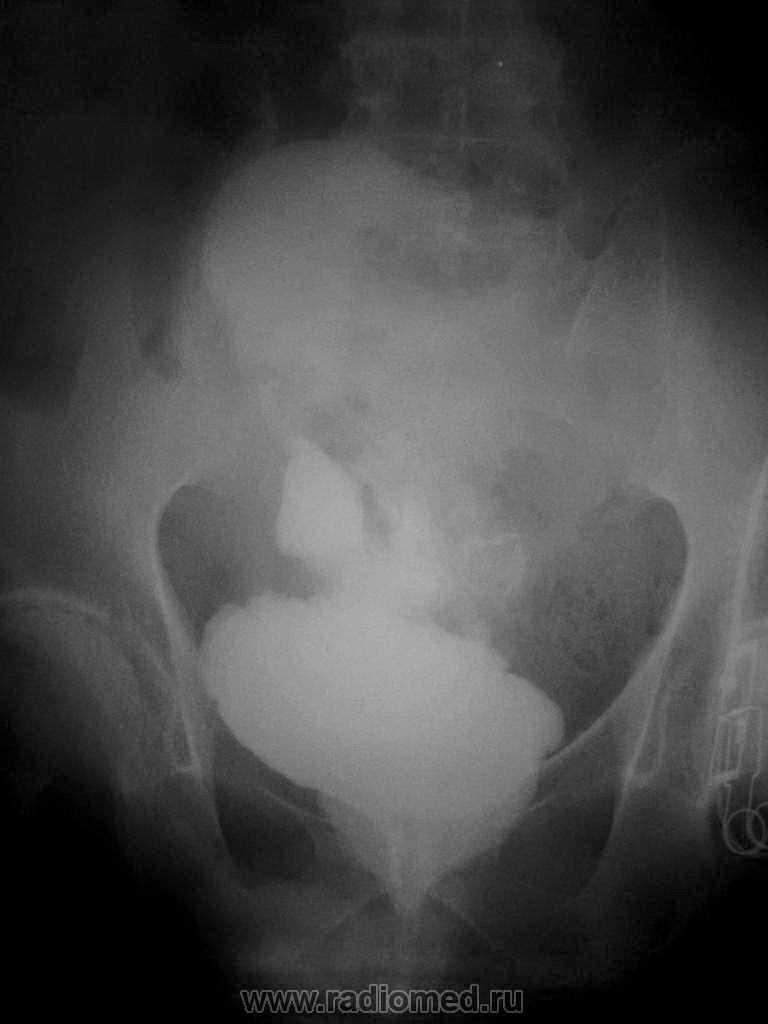

Медицинские изображения и примеры эксреторной цистографии